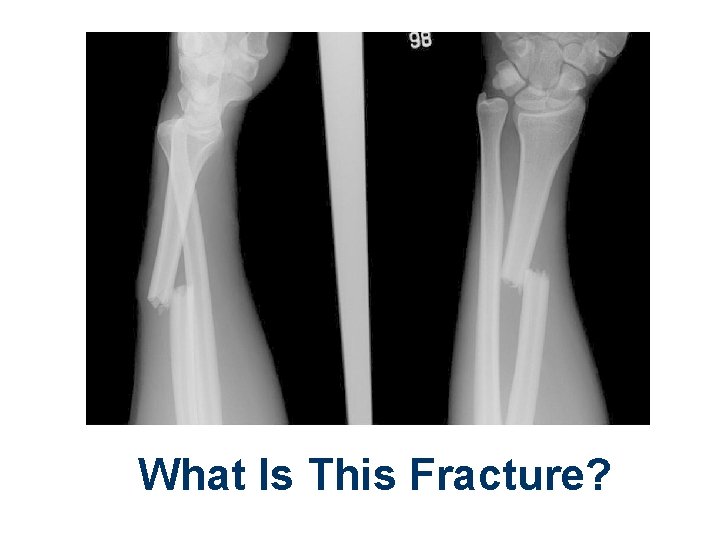

What Is This Fracture?

Unstable Mid-shaft Forearm Fracture How Should It Be Immobilized?